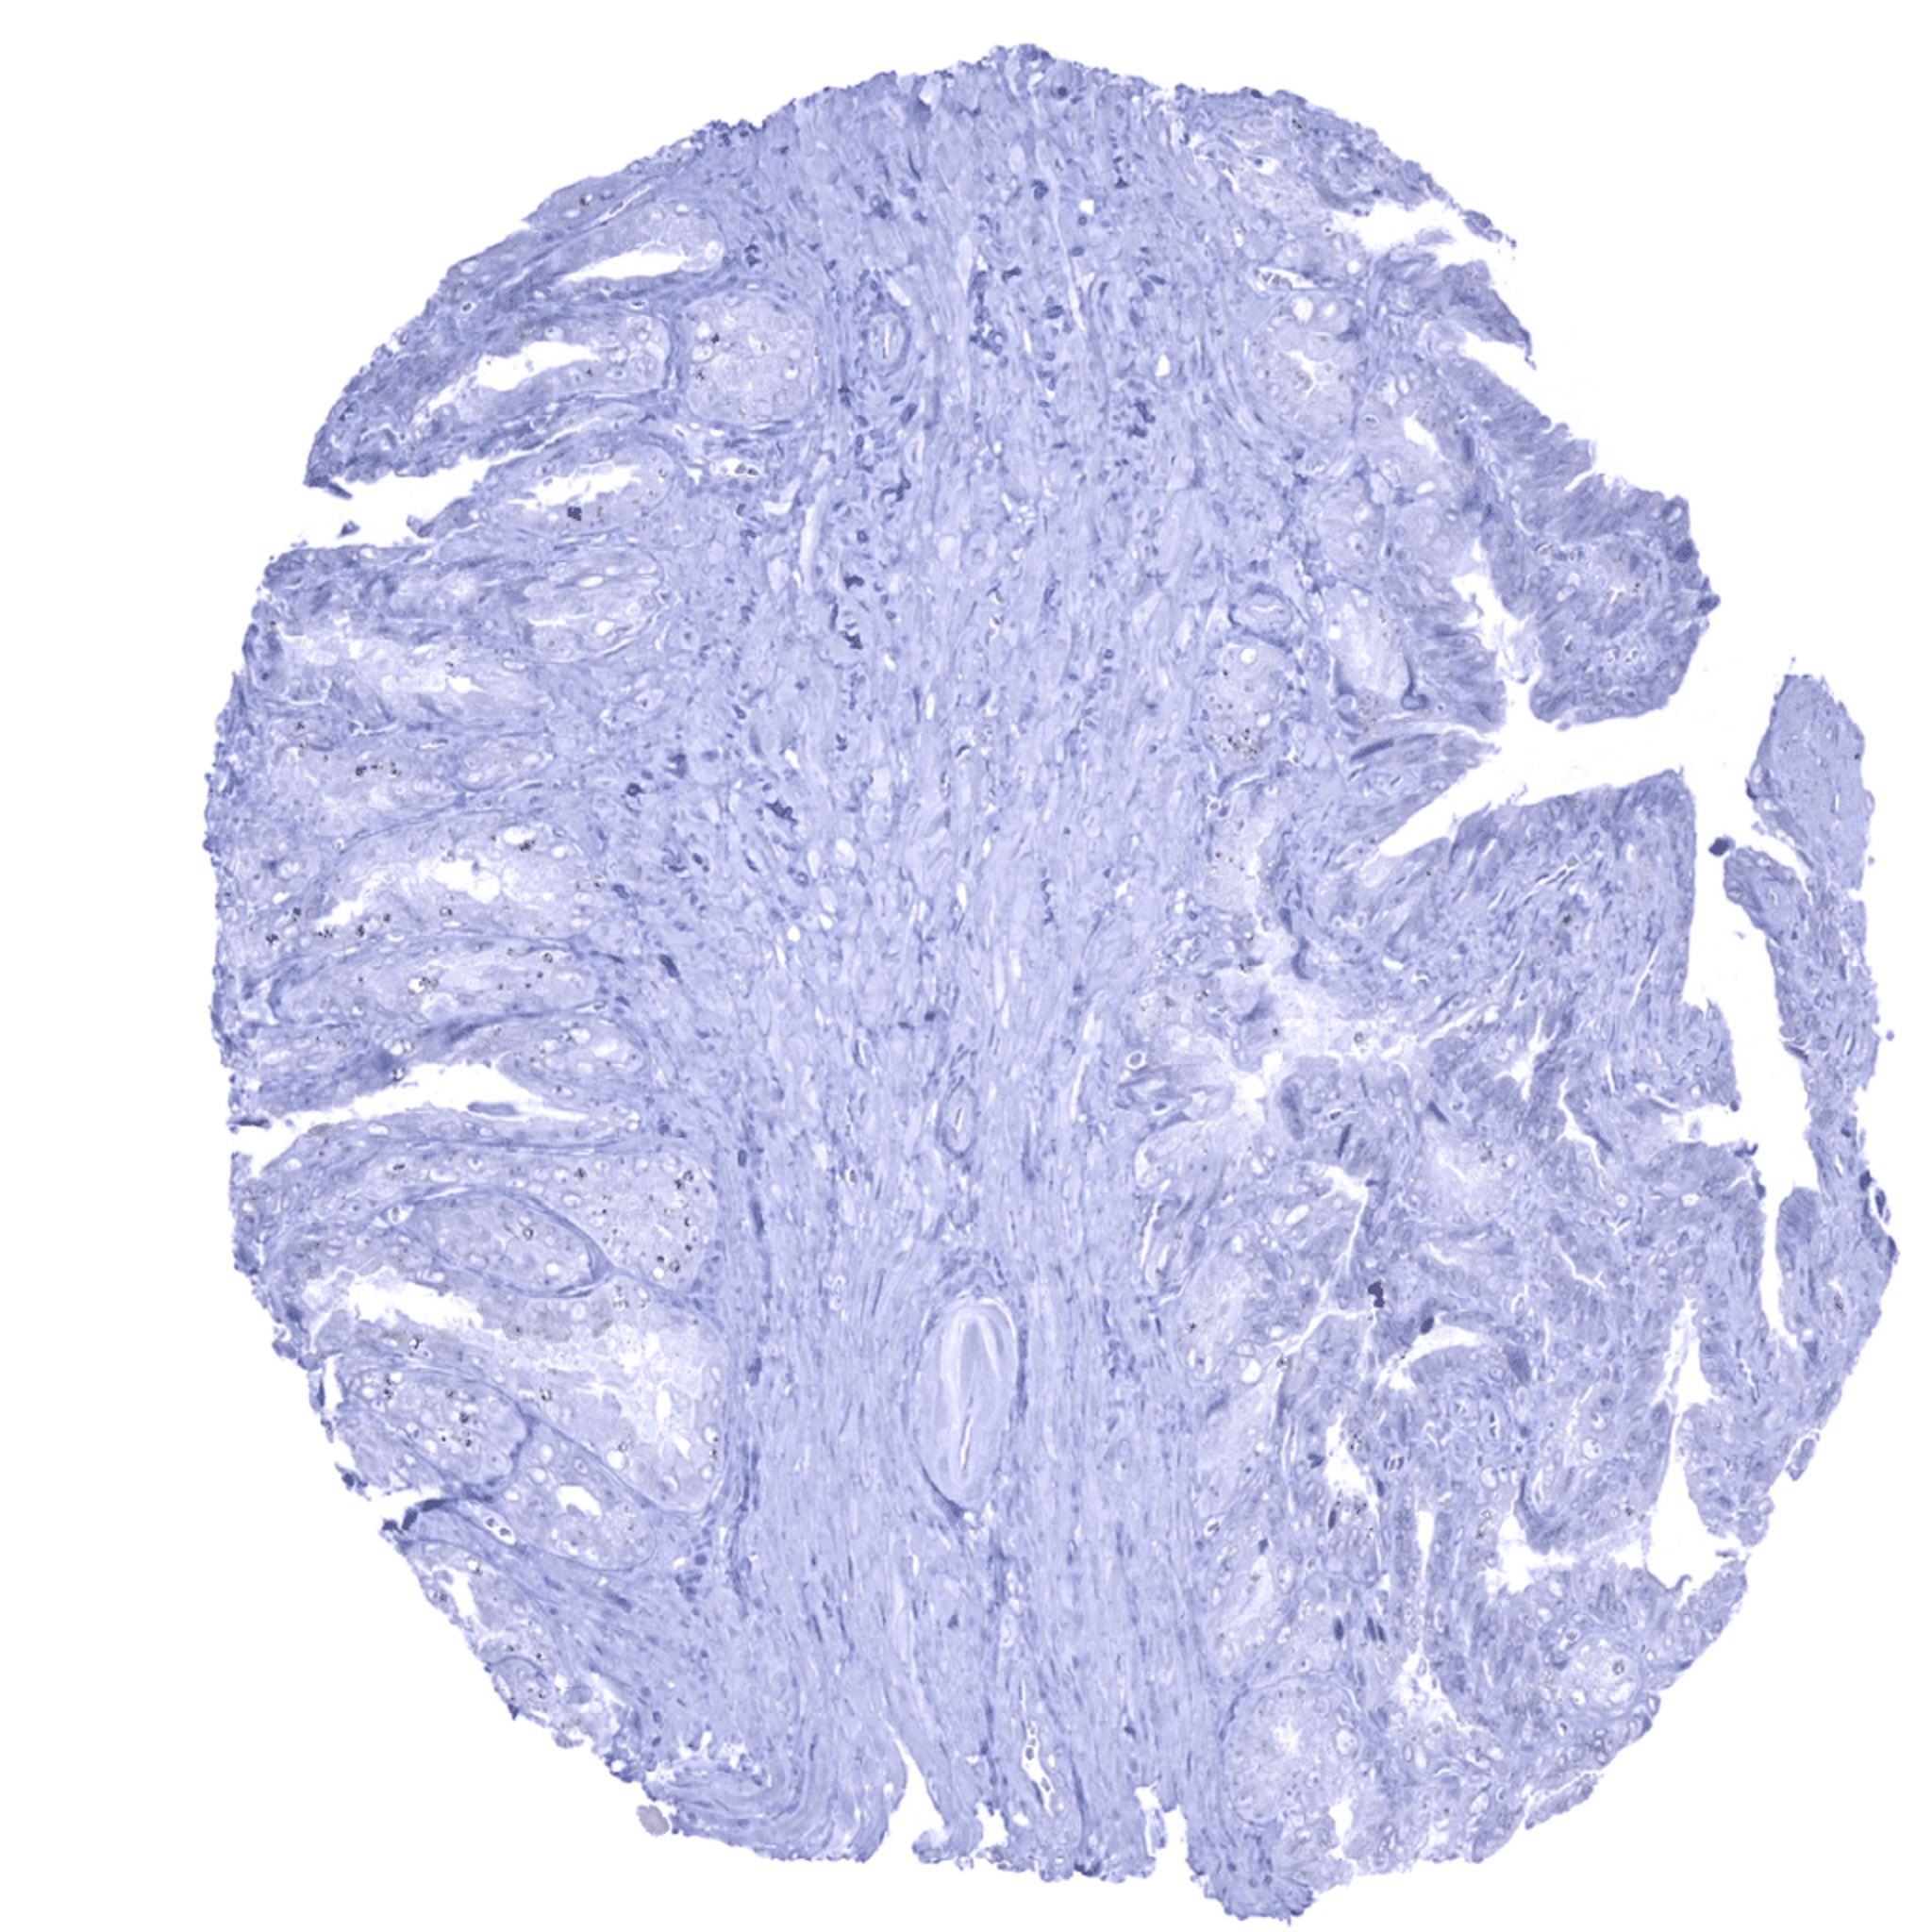

Uterus, ectocervix – UPK1B staining is lacking